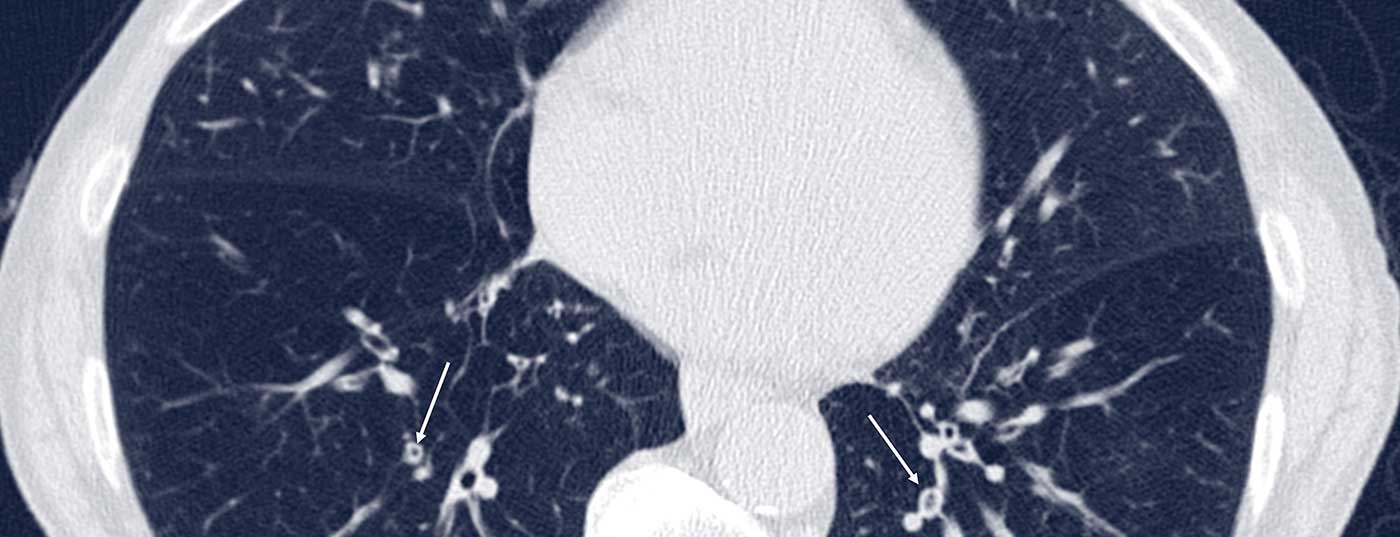

Pulmonale Infektionen verschärfen häufig die Symptomatik bei COPD-Patienten. Röntgen und CT helfen, Differenzialdiagnosen zu stellen und das individuelle Exazerbationsrisiko besser einzuschätzen.